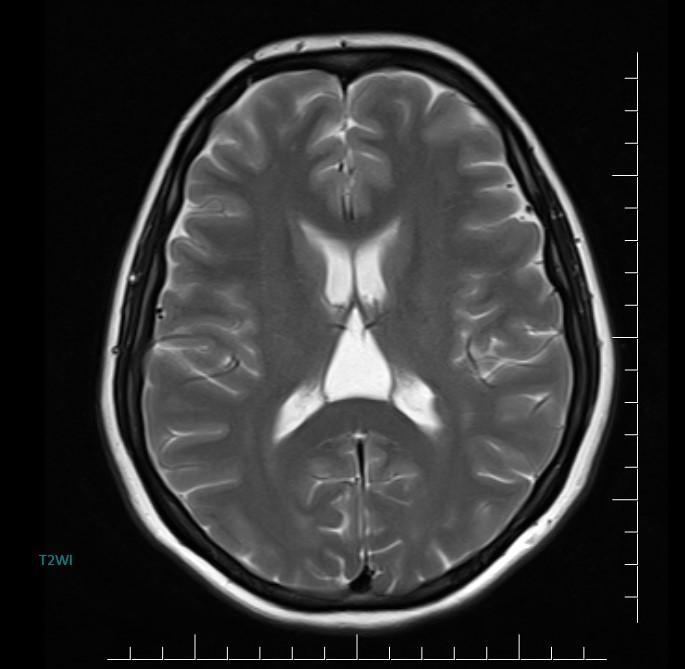

MR images incidentally revealed a triangular-shaped CSF space between the lateral ventricles (arrows).

Axial MR/CT image shows a triangular-shaped CSF space situated behind the foramen of Monro, between the lateral ventricles. Coronal image demonstrates the elevated and splayed fornices.